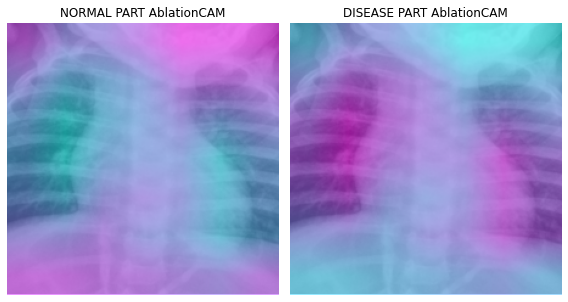

fig, (ax1,ax2) = plt.subplots(1,2)

dls.train.decode((x,))[0].squeeze().show(ax=ax1)

ax1.imshow(-cam_ablationcam.squeeze(),alpha=0.5,extent=(0,224,224,0),interpolation='bilinear',cmap='cool')

ax1.set_title("NORMAL PART AblationCAM")

#

dls.train.decode((x,))[0].squeeze().show(ax=ax2)

ax2.imshow(cam_ablationcam.squeeze(),alpha=0.5,extent=(0,224,224,0),interpolation='bilinear',cmap='cool')

ax2.set_title("DISEASE PART AblationCAM")

fig.set_figwidth(8)

fig.set_figheight(8)

fig.tight_layout()